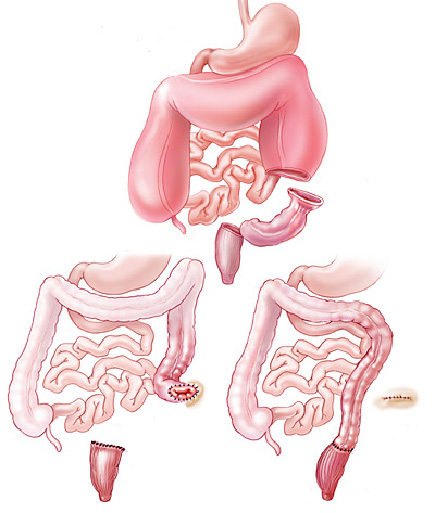

Colonoscopia é o exame endoscópico do cólon (intestino grosso) e muitas vezes também do íleo terminal (porção final do intestino delgado). Além da inspeção da superfície intestinal, a colonoscopia permite também a realização de biópsias que podem ser úteis no estabelecimento do diagnóstico. Procedimentos terapêuticos também podem ser realizados durante a colonoscopia, entre eles o mais frequente é a remoção de pólipos (polipectomia).

Após o preparo do cólon, o paciente é levado à sala de exame onde será sedado. A sedação é realizada por via endovenosa e ajuda o paciente a dormir e relaxar. O colonoscópio é então introduzido pelo reto até o ceco (porção inicial do cólon) ou até o íleo terminal (porção final do intestino delgado). Durante a retirada do aparelho é feita uma minuciosa inspeção identificando as eventuais alterações.

Estenose do intestino é o estreitamento parcial ou total do intestino grosso (ou raramente do intestino delgado) que impede a progressão do conteúdo através do mesmo.

Estenose do intestino pode acontecer por 2 causas principais:

1- Tumores do intestino: alguns tumores do intestino podem crescer ao ponto de causar a obstrução do órgão. Nestes casos geralmente realiza-se cirurgia para se retirar a parte do intestino acometida. Nos casos muito avançados pode-se passar através da colonoscopia uma prótese autoexpansível para desobstrução. Esta prótese também pode ser colocada para melhorar o estado físico e o preparo do paciente antes de ser realizado uma cirurgia definitiva.

2- Estenose benigna: algumas inflamações do intestino podem ao cicatrizar levar a retração da parede do órgão e fechamento do mesmo. Doenças como a Retocolite Ulcerativa, a Doença de Crohn, a Colite por radioterapia, e algumas infecções do intestino podem levar a este processo. Existem também as estenoses pós operatórias que acontecem quando ocorre uma cicatrização exagerada da parede do intestino remanescente após a cirurgia.

Nos casos de estenoses benignas do intestino realiza-se a dilatação endoscópica da região com balão do tipo hidrostático.

Nos casos onde não há melhora com as dilatações realiza-se o tratamento cirúrgico do problema através do procedimento chamado de colectomia parcial.